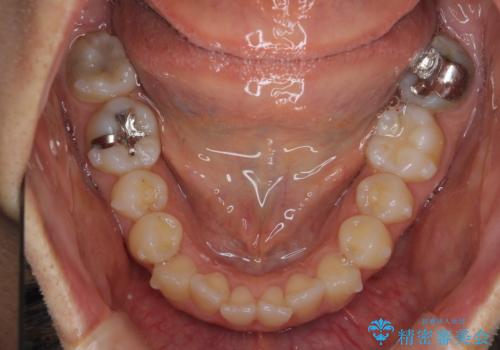

前歯のがたつきをしっかり治すマウスピース矯正

- 前歯のガタガタをきれいに並べたい、と希望され来院されました。

マウスピース矯正インビザラインのクリンチェックを用いて治療前にしっかりと歯並びのゴールのシミュレーションを行い、治療を開始します。

がたつきのないきれいな歯並びに仕上げることができ、満足いただくことができました。